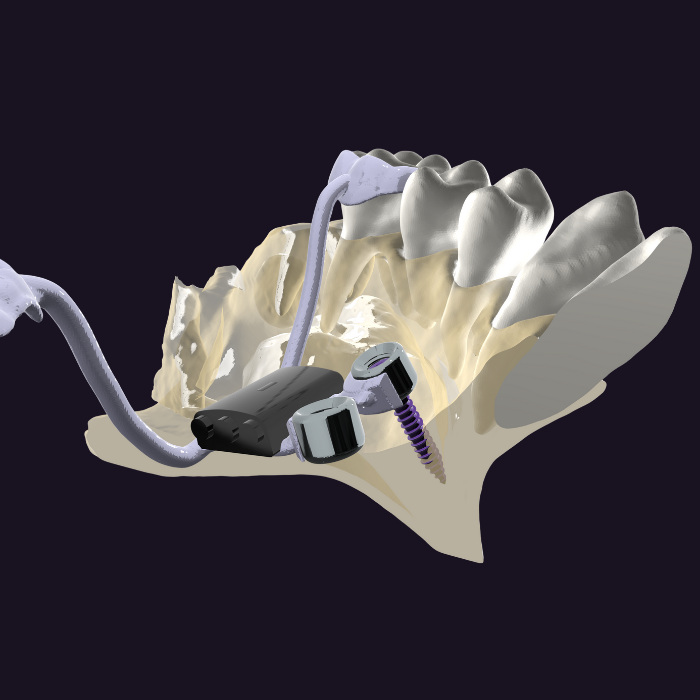

MARPE Yerleştirme Protokolü

5 adımlık pratik yerleştirme protokolü. CBCT tabanlı planlama, tork kontrollü yerleştirme ve retansiyon süreçleri.

- CBCT ile klinik değerlendirme

- Tork ve devir kontrollü yerleştirme

- Aktivasyon protokolü (1. gün 2 tur, sonra günde 1 tur)

- 3-6 ay retansiyon dönemi